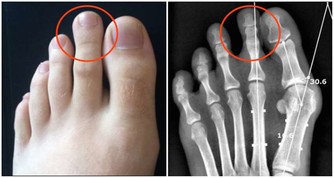

三、氣胸

氣胸是胸外科常見的疾病之一。常常在跑步、拿重物或體力勞動後發生,可發生於無明顯病變的健康人,

尤以體型瘦長的青年多見,也可發生在其他肺部疾病患者。

最典型的症狀是突發的胸痛,多為針刺樣或刀割樣疼痛,持續時間較短,可伴有呼吸困難、刺激性咳嗽等症狀,嚴重者可出現煩躁乃至休克的表現。

如發生氣胸,應馬上臥床休息,充分吸氧,嚴重者需及時就診,由胸外科醫生及時治療。